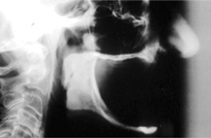

Fig 1. 81-year-old patient had severe mandibular atrophy from many years of denture wear and had a history of inability to manage a mandibular prosthesis.

Figure 1

The Toronto Conference in 1982, chaired by Professor George Zarb and presented by Professor Per-Ingvar Brånemark, was a seminal event that changed edentulous treatment planning concepts irrevocably. No longer was it necessary to rebuild lost bone through grafting alone in either arch. The severely atrophic mandible, for example, could be treated with as few as four implants used to support a bone-sparing prosthesis through integrated tooth analogs, as demonstrated in Figure 1 through Figure 3. Here, an 81-year-old patient presented with severe mandibular atrophy (Figure 1) from denture wear since a very young age and had a history of being unable to manage a mandibular prosthesis despite numerous attempts at new denture construction. Four vertical machined-surface osseointegrated implants were placed in 1983 by Professor Brånemark, and all four penetrated the inferior cortex up to 3 mm to 4 mm in depth, as shown on the immediate postoperative panoramic film (Figure 2). At 4 years and 5 months, reparative bone had formed to the apices of all implants (Figure 3), and all of them remained in uncompromised function until the patient passed away at age 90.